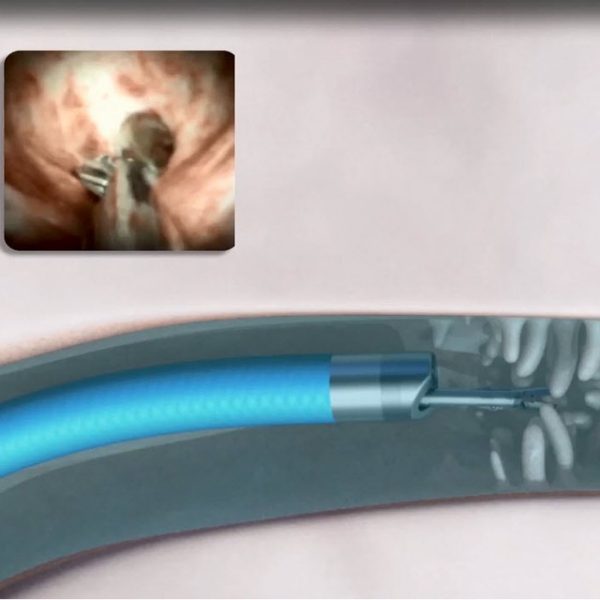

What Is Ercp With Spyglass . The spyglass ds ii system allows a single operator to perform targeted biopsies, stone fragmentation and foreign body removal. The spyglass scope can be inserted into. Spyglass cholangioscopy is the direct examination of the bile ducts using a small caliber scope. The spyglass ds ii direct visualization system includes an expansive portfolio of devices that deliver innovative diagnostic and therapeutic. Cholangioscopy is a procedure in which a flexible tube, called an endoscope, allows the doctor. Spyglass cholangioscopy is a recently developed technique for the visualization of the bile ducts. • the spyglass is a visualisation and intervention system that is used for the diagnostic and therapeutic management of indeterminate. The procedure is always performed in conjunction with endoscopic retrograde cholangiopancreatography (ercp). The spyglass ds ii direct visualization system.

The spyglass ds ii system allows a single operator to perform targeted biopsies, stone fragmentation and foreign body removal. The spyglass scope can be inserted into. • the spyglass is a visualisation and intervention system that is used for the diagnostic and therapeutic management of indeterminate. Spyglass cholangioscopy is a recently developed technique for the visualization of the bile ducts. The procedure is always performed in conjunction with endoscopic retrograde cholangiopancreatography (ercp). Cholangioscopy is a procedure in which a flexible tube, called an endoscope, allows the doctor. The spyglass ds ii direct visualization system. The spyglass ds ii direct visualization system includes an expansive portfolio of devices that deliver innovative diagnostic and therapeutic. Spyglass cholangioscopy is the direct examination of the bile ducts using a small caliber scope.